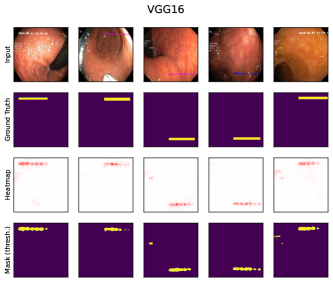

6.4 Spatial Bias Localization

To spatially localize biases in input space with CAVs, we compute local explanations for the element-wise product of latent activations and concept direction (see Eq. 2). We use the controlled artifacts, specifically timestamp (HyperKvasir) and micropscope (ISIC2019) with ground truth concept localization masks for evaluation. We compute (1) the percentage of relevance within the ground truth mask and (2) the Jaccard index, or Intersection over Union (IoU), of the binarized localization mask with the ground truth. In Fig. 9, we report both metrics using CAVs computed on different layers of VGG16 and ResNet50. The layer choice for concept representations is key, as for example middle layers perform better to localize timestamps and earlier layers are more effective to localize the microscope. In comparison with Fig.7, we find that the optimal layer for bias localization may differ from the one for sample retrieval. Interestingly, the IoU for the microscope artifact is consistently low, as models primarily focus on the border of the circle instead of the entire area, as indicated by qualitative results in Appendix A.6.3. Unlike artifact relevance, the IoU metric also measures how much of the expected areas the computed mask does not cover.